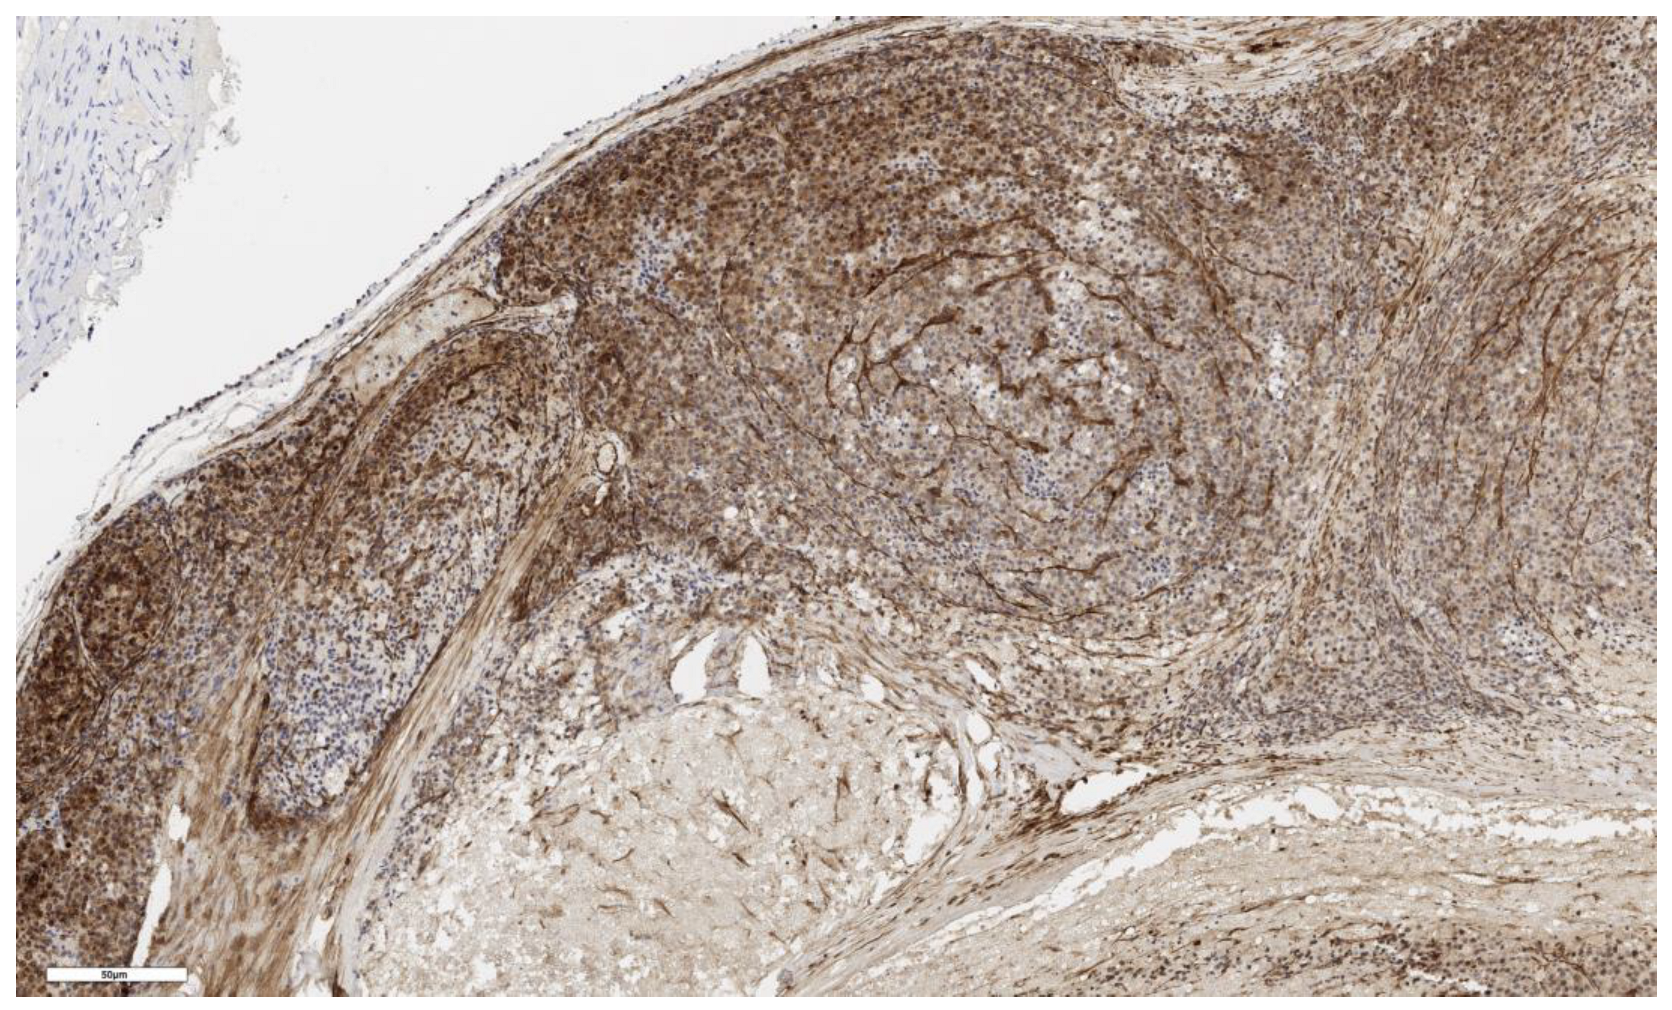

3.1. Analysis of CD90 Marker Expression

3.2. Analysis of LGR5 Marker Expression